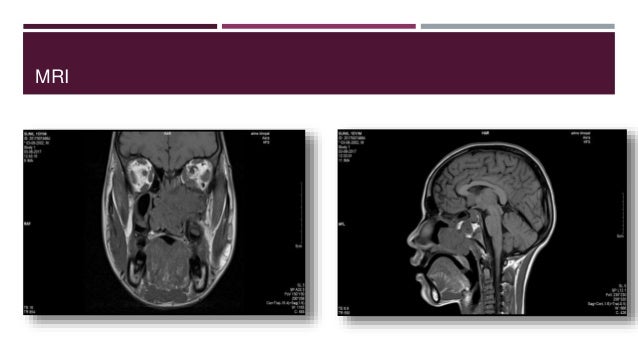

21. 21. MRI  Characteristic – Salt & Pepper appearance due to flow voids  It aids in differentiation of tumour in – Orbit , Cavernous sinus , Middle cranial fossa , Infratemporal region

22. 22. MRI